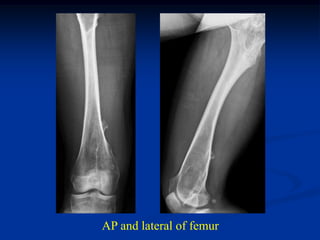

Case #625.1                 Multiple hereditary exostoses

50 yr old female with short stature and R hip pain for years

AP and lateral of right hip

AP and lat tibia

Proximal humeral x-rays

AP and lateral of femur